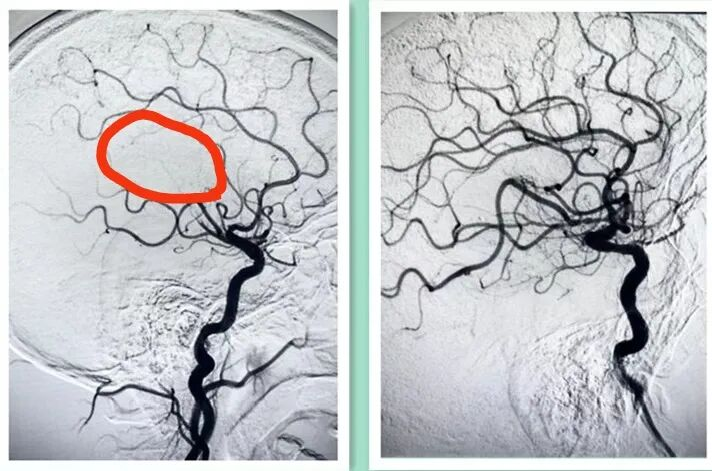

右侧额顶叶新发脑梗死 右侧大脑中动脉 远端分支少

神经内科武钟毅主任及孙玉琴主治医师行脑血管造影,术中发现患者右侧大脑中动脉上干闭塞,采用SWIM技术进行大脑中动脉取栓术,使右侧大脑中动脉血流达到3级再通。

右侧大脑中动脉上干闭塞(术前) 右侧大脑中动脉上干闭塞(术后)